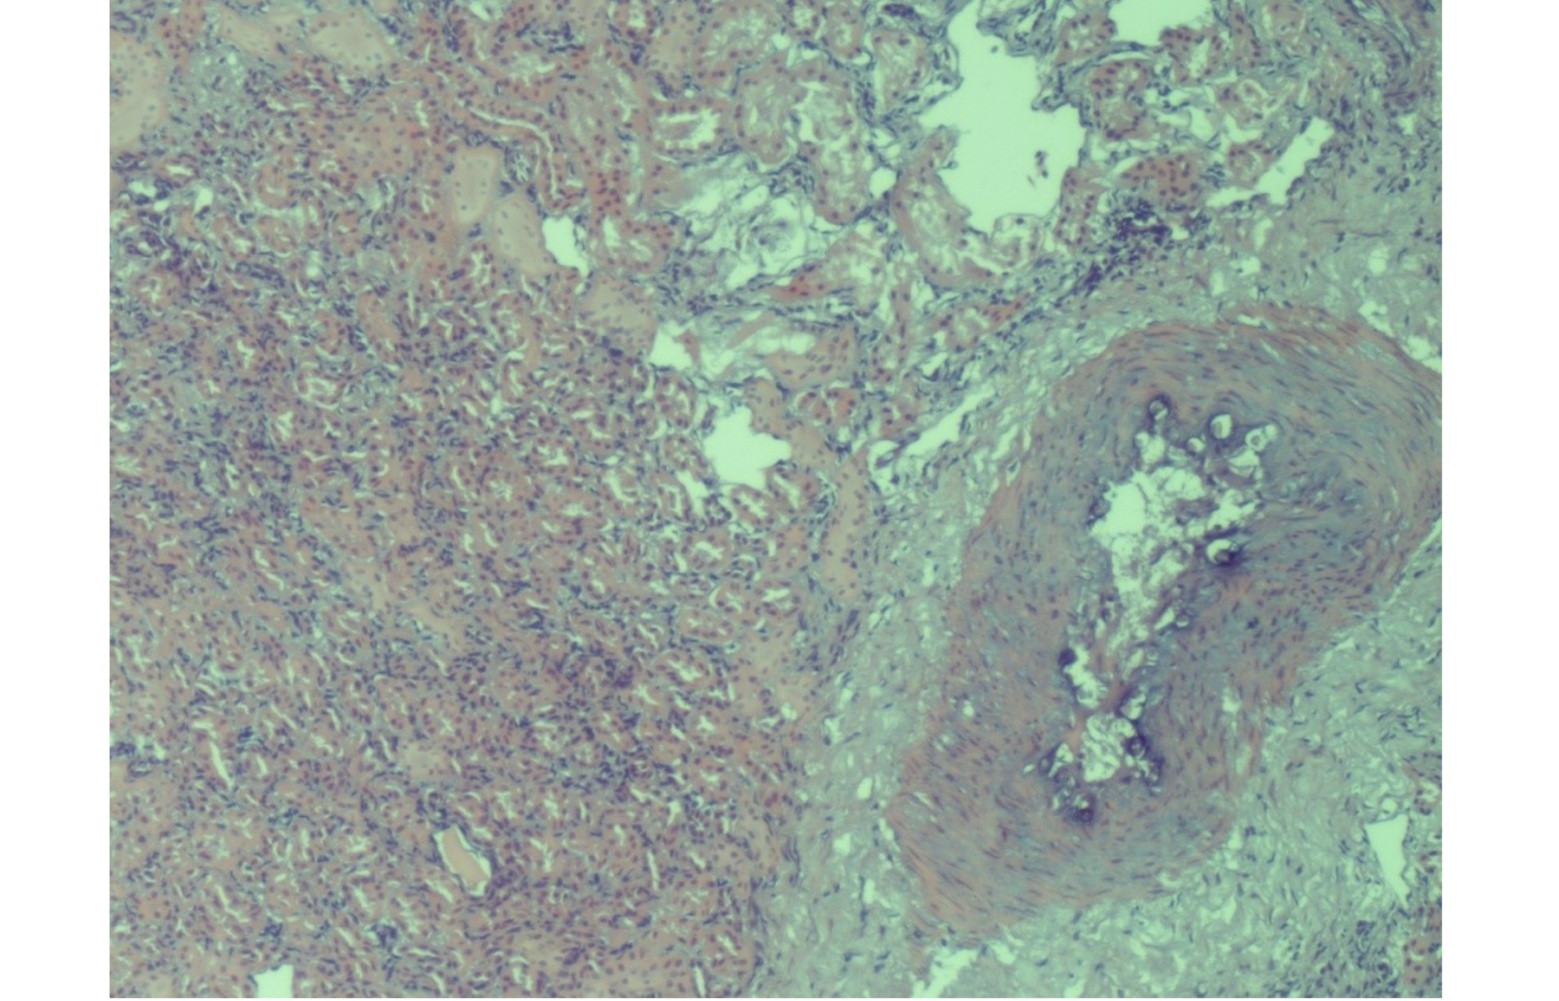

Furthermore, evaluation of the histological kidney sections revealed marked proliferation of Bowman’s capsule cells, localized to part of the capsule’s circumference, forming the characteristic crescent-shaped structures. Tubulonephrosis and glomerulopathy were also evident (Figure 2).The progressive proliferation of the crescent led to obliteration of the glomerular tuft, resulting in irreversible destruction of the glomerulus and subsequent nephron atrophy (Figure 3). Additionally, perivascular sclerosis was observed in small- and medium-calibre arterial vessels (Figure 4).

Figure. 2. Kidney: great proliferation of Bowman’s capsule cells. Tubulonephrosis and glomerulopathy HE (Hematoxilin Eosin) x 20.

Figure. 3. Kidney: nephron atrophy and progressive tubule interstitial glomerular-nephritis. HE (Hematoxilin Eosin) x 20.

Figure. 4. Kidney: perivascular sclerosis in the small and medium-calibre arterial vessels. HE (Hematoxilin Eosin) x 10.